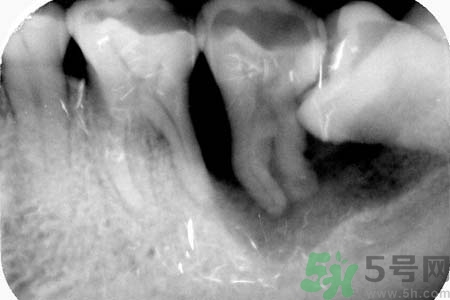

智齒能不拔嗎?智齒長在大家牙槽的最里面,比較不容易清潔干凈,還容易發(fā)炎。智齒還會影響人們的臉型,一般去醫(yī)院醫(yī)生都會建議拔掉智齒。關(guān)于智齒拔了好不好?智齒能不拔嗎?小編為您一一解答。

要不要拔智齒完全取決于大家的智齒長得怎么樣,事實上智齒和別的牙沒有質(zhì)的區(qū)別。只不過因為它的位置特殊,很容易長歪,而且在功能上又沒有特別的意義,所以醫(yī)生才建議拔掉。

智齒長在牙槽最里邊,平時清潔很難徹底,而且如果長歪了就更難清潔,所以就特別容易齲壞,慢慢發(fā)展成深齲,甚至感染導(dǎo)致炎癥膿腫等等。拔掉它只是為了絕后患,如果你的智齒長得好好的,就不要拔掉,畢竟拔牙是有創(chuàng)的手術(shù),會流血,而且24小時內(nèi)不能用那一邊吃東西,也挺麻煩的。拔牙一定要去正規(guī)醫(yī)院或診所,因涉及血液,胡亂去小攤可能因不慎感染肝炎或艾滋病。